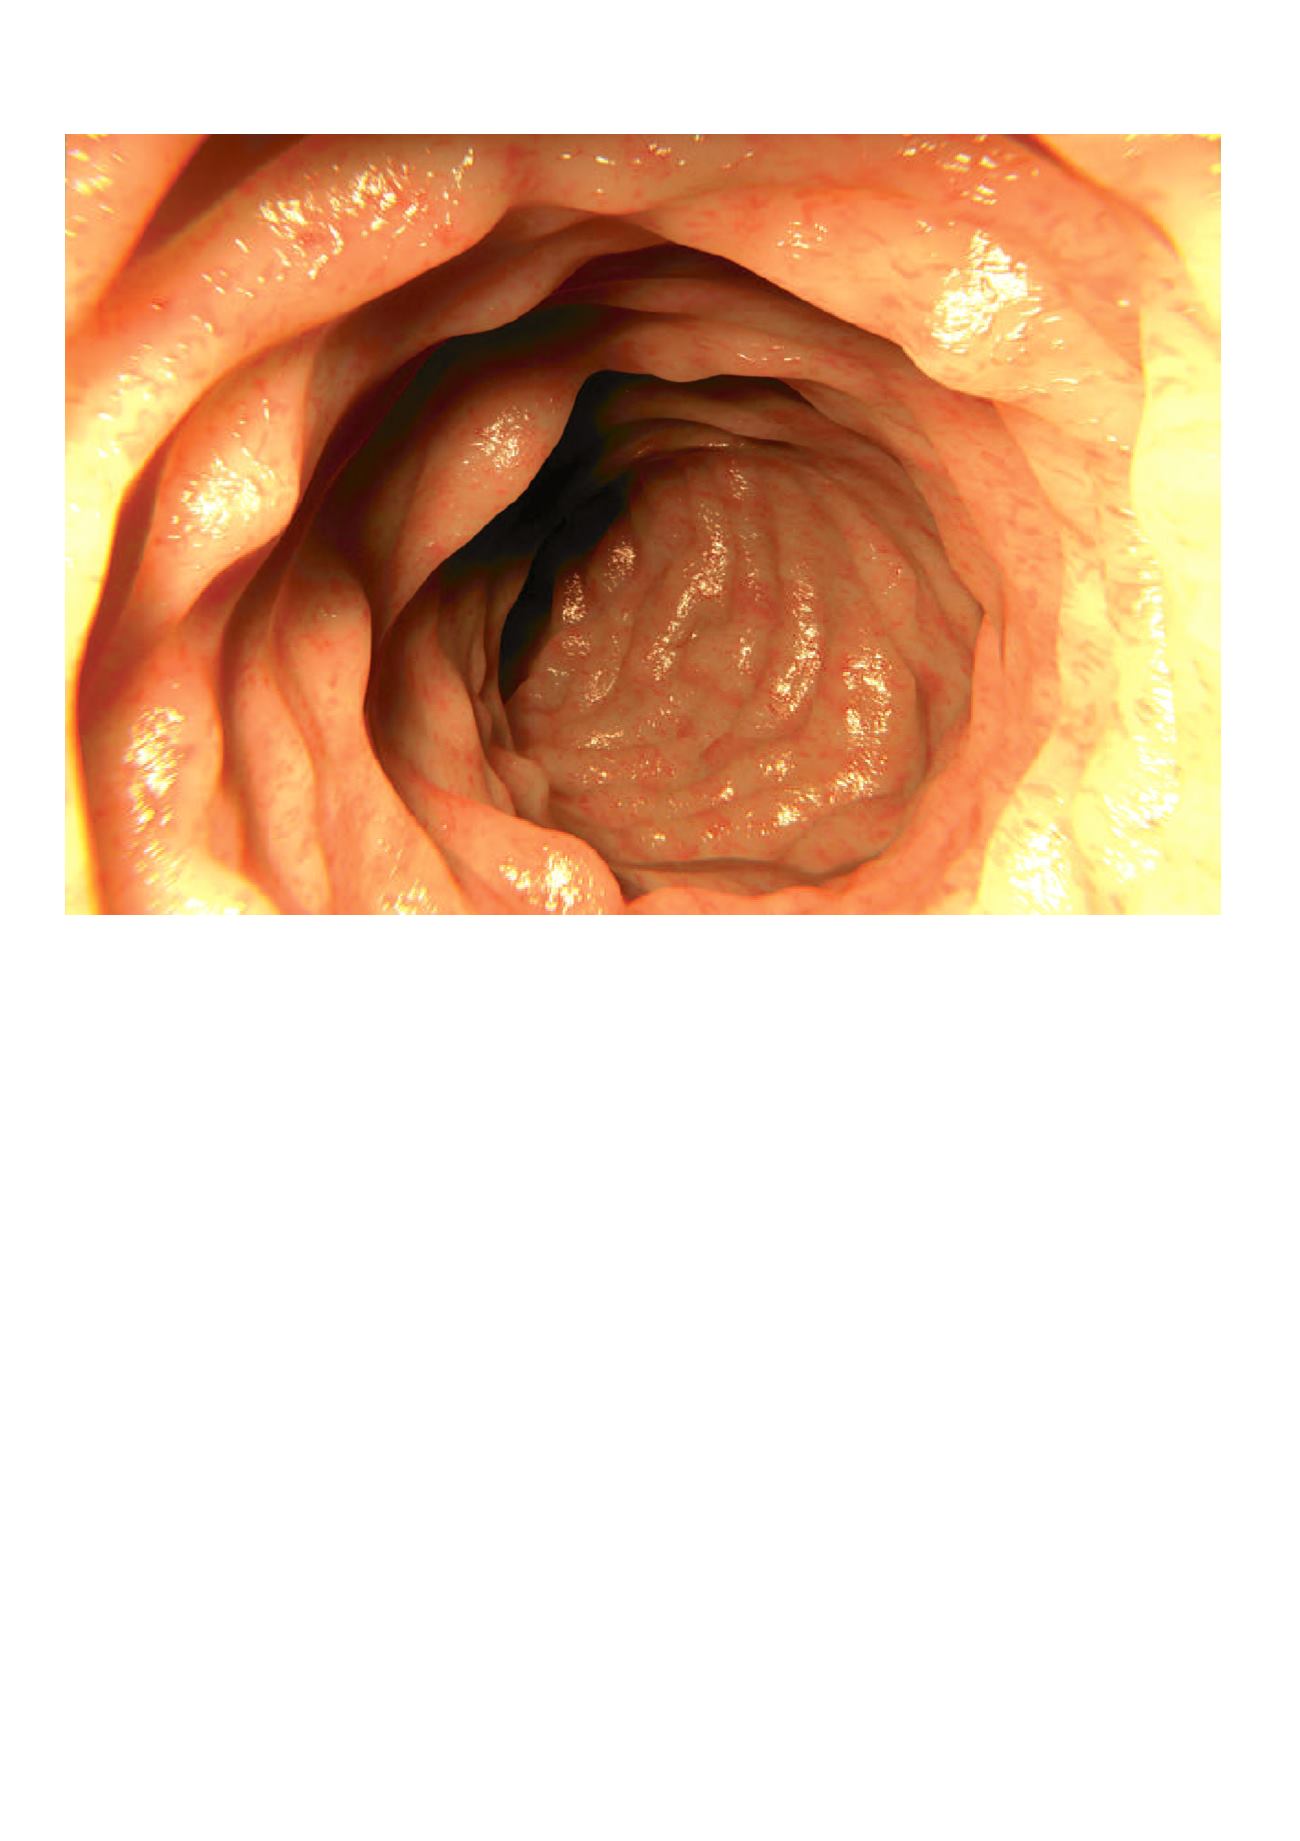

Chronisch ontstoken darmen

Gezonde dikke darm